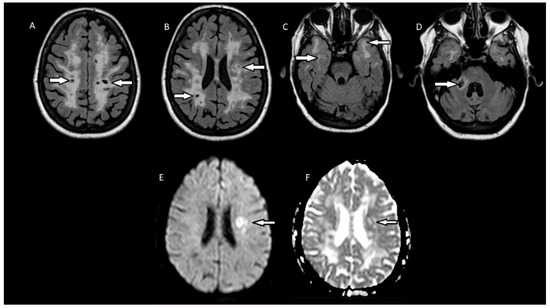

2. Case Report